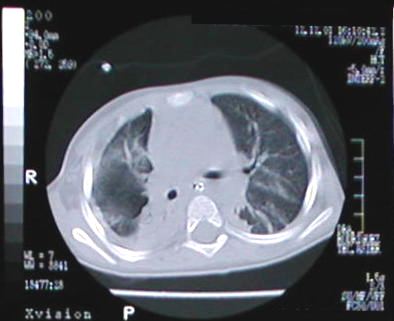

Corte Tomográfico " 1 "

Corte nivel sub carinal de traquea:

Parenquima pulmonar lado derecho en fase neumonica resolutiva, engrosamiento pleural y liquido pleural escaso, del lado izquierdo note el parenquima con areas neumonicas dispersas.